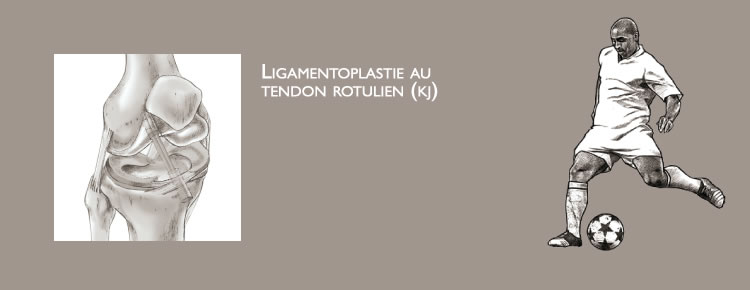

L’intervention : Ligamentoplastie au tendon rotulien (kj)

L’intervention consiste à remplacer le ligament rompu. Ce geste est réalisé sous arthroscopie, c’est à dire sans ouvrir l’articulation. Une petite caméra est introduite dans l’articulation pour visualiser la rupture du ligament et vérifier les ménisques et le cartilage. Des petits instruments sont utilisés par la suite pour réaliser un tunnel au fémur et un autre au tibia (figure 3).

Une incision courte est réalisée en avant du genou pour prélever une partie du tendon rotulien avec une petite baguette osseuse de part et d’autre (figure 3). Le prélèvement est alors passé à l’intérieur du genou et fixé dans les tunnels osseux par des vis résorbables. Il remplace ainsi le ligament rompu (figures 4 et 7).